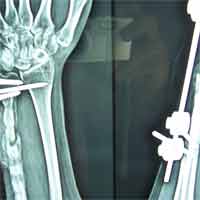

Case:4 Comminuted Intra – Articular Lower End Fracture Radius

A patient, aged 46 years following vehicular accident came with swollen painful wrist & hand. He had been diagnosed to have closed comminuted fracture lower end of right Radius. He was treated operatively with closed reduction & ‘K’ wiring under regional Anaesthesia.

Pre-Op

Pre-op Lateral

Post-op AP

One and Half Months Follow-Up